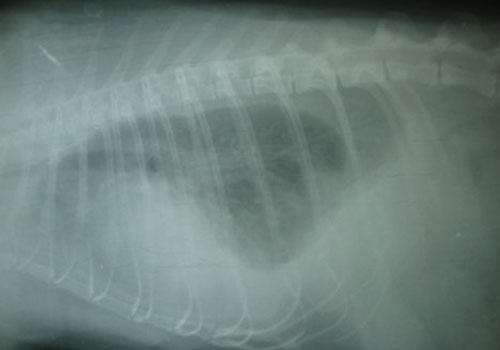

乳糜胸拍片